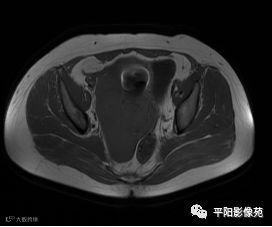

MRI表现

T2轴位

T2抑脂序列轴位

(宫腔内见金属节育环伪影)宫颈区见不规则形等T1稍长T2信号软组织肿块,DWI序列呈明显高信号,大小约为3.87cmX2.64cm,双侧宫颈基质低信号环连续性中断,病灶向子宫右后上方生长,周围脂肪间隙模糊,增强扫描明显强化,强化程度低于子宫及宫颈实质;子宫后方、子宫直肠间隙见不规则形长T1长T2信号软组织肿块,DWI序列呈高信号,大小约10.12cmX4.82cmX10.29cm,病灶呈分叶状,向下方生长与宫颈分界不清,与直肠分界尚清,增强扫描明显不均匀强化。